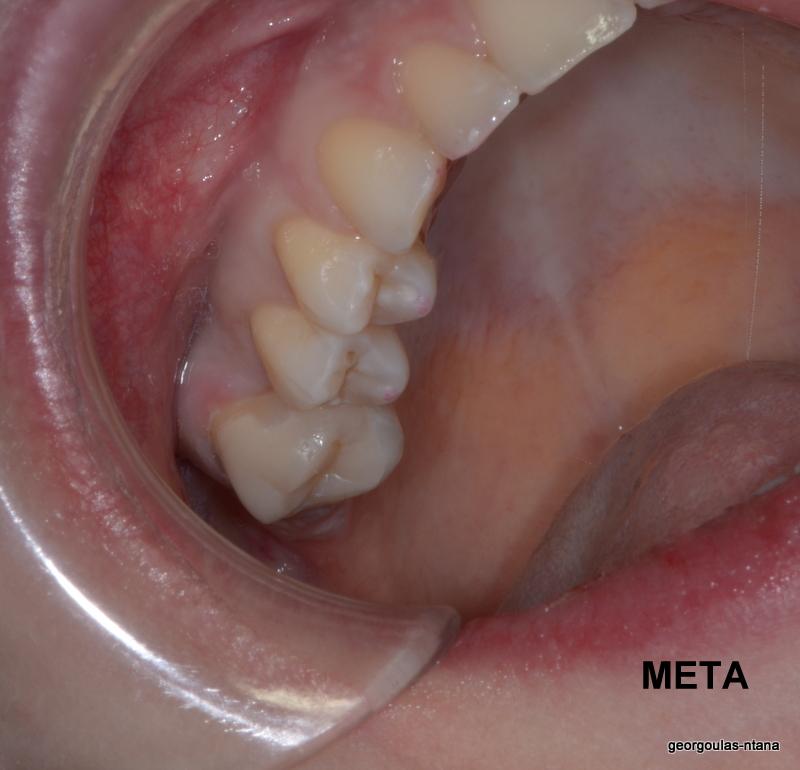

ΠΡΟΣΘΕΤΙΚΗ ΑΠΟΚΑΤΑΣΤΑΣΗ ΣΤΗΝ ΑΝΩ Κ ΚΑΤΩ ΓΝΑΘΟ ΚΑΙ ΤΟΠΟΘΕΤΗΣΗ ΕΜΦΥΤΕΥΜΑΤΩΝ ΜΕ ΚΛΕΙΣΤΗ ΑΝΥΨΩΣΗ ΙΓΜΟΡΕΙΟΥ

περισσότερα...